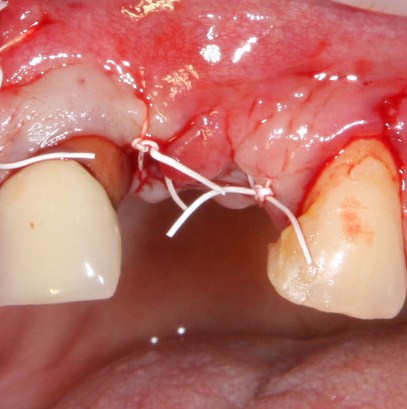

К счастью, уже через 6 недель после операции вдруг выяснилось, что ничего исправлять не нужно:

Фактически, нам осталось лишь дождаться приемлемого уровня остеоинтеграции имплантатов,  — примерно 2-3 месяца, — и можно переходить к постоянному протезированию.

Через три месяца мы сняли коронки с имплантатов, чтобы оценить качество формирования десневого контура:

С этого момента можно перестать переживать — десневой контур сформировался правильно, мы получили достаточный объём и качество окружающей платформу имплантата десны. Можно приступать к изготовлению постоянной протетики. Подрядчиком стала зуботехническая лаборатория French Creative, одна из топовых лабораторий Москвы.